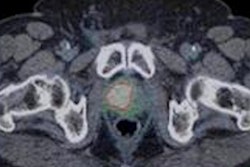

Australian researchers analyzed some 300 men with biopsy-proven prostate cancer and high-risk features and found that PSMA-PET/CT was 27% more accurate than CT and bone scans in detailing the spread of prostate cancer throughout the body. In addition, the hybrid modality appropriately changed the course of treatment for more than twice as many prostate cancer patents as CT and bone scans combined.

In reviewing the images, PSMA-PET/CT had statistically significant higher accuracy and sensitivity for detecting the spread of cancer compared with conventional CT and bone scans (p < 0.0001). The difference in accuracy was due primarily to PSMA-PET/CT's ability to find smaller tumors, the authors noted. Conventional imaging also failed to detect metastases in 29 patients.

| Sensitivity | 38% | 85% | < 0.0001* |

| Specificity | 91% | 98% | NS |

| Accuracy | 65% | 92% | < 0.0001* |